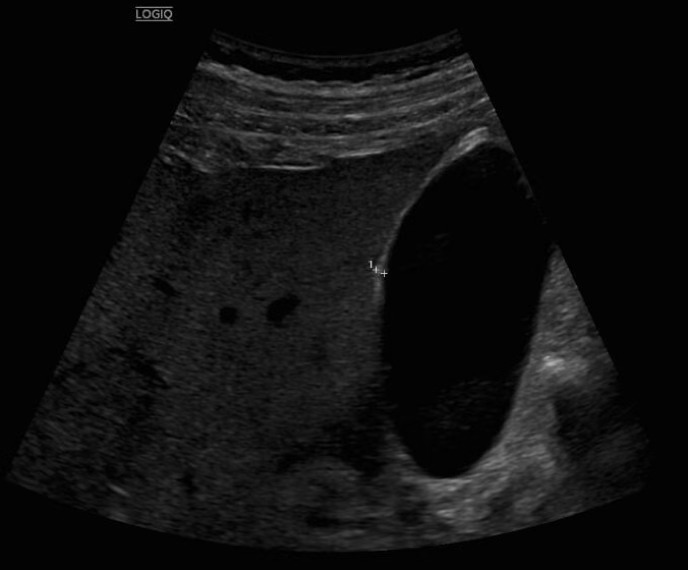

La ecografía abdominal urgente muestra engrosamiento parietal del colon descendente-sigma-recto, aumento de ecogenicidad de la grasa pericólica e hiperemia, compatibles con colitis izquierda.

Se realiza tomografía computarizada abdominal con contraste, identificando un absceso pericólico de 2,8×5,7 cm en sigma, cambios inflamatorios mesentéricos y signos sugestivos de pileflebitis.

La ecografía abdominal urgente permitió identificar precozmente un proceso inflamatorio colónico, orientar el diagnóstico diferencial y priorizar la realización rápida de tomografía, detectando una complicación abscesificada. Este caso destaca el valor de la ecografía en Medicina de Familia como herramienta accesible, resolutiva y clave para mejorar la seguridad, optimizar derivaciones y reducir tiempos asistenciales.